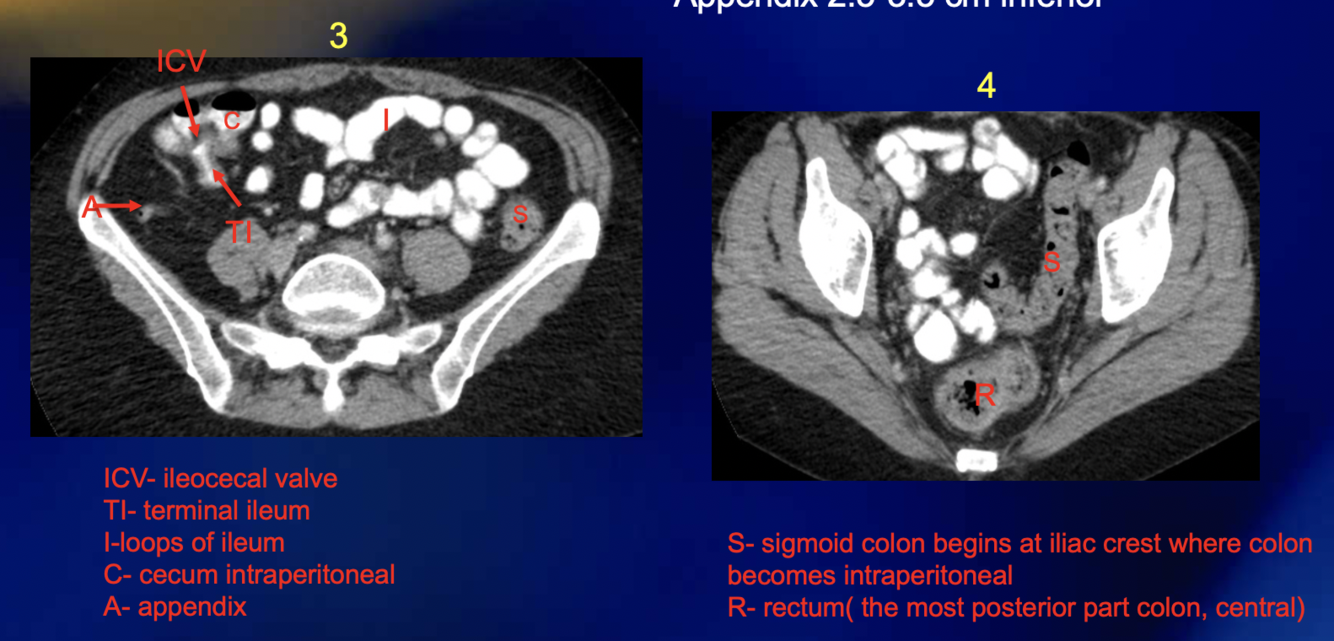

If a person has appendicitis and their appendix is retrocecal, they will likely present with […] pain

If a person has appendicitis and their appendix is pelvic, they will likely present with […] pain

Shoulder

RLQ

The appendix is [….]peritoneal

Intra